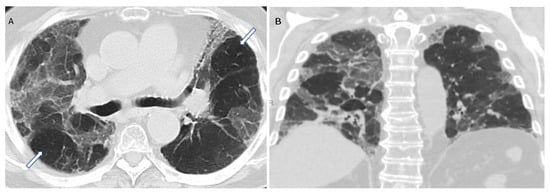

“Mosaic attenuation” is a term reserved for inspiratory phase CT. It is defined as sharply demarcated areas of low and high attenuation. Mosaic attenuation can be seen in vascular diseases, airway diseases, or infiltrative diseases [35] (Figure 2 and Figure 3). As opposed to mosaic attenuation, the term “air trapping” is only used on expiratory phase CT (Figure 2, Figure 3 and Figure 4). This term represents abnormal air retention distal to airway obstruction and manifests as areas of lucent lung on a background of normal relatively high attenuation lung parenchyma on expiratory imaging [3]. Like mosaic attenuation, the term “mosaic perfusion” (Figure 5) is also reserved for inspiratory CT. In mosaic perfusion abnormality, one may see a smaller caliber of the pulmonary vasculature within areas of low attenuation compared to normal vessel caliber in areas of higher attenuation. However, mosaic perfusion can be seen because of a vascular disease (pure perfusion abnormality), or in airway diseases where there is mosaic perfusion secondary to abnormal ventilation. Hence, the role of expiratory CT to aid differentiation of mosaic perfusion is secondary to vascular diseases from airway disease. If there is a similar gradient of attenuation between low and high attenuation areas on inspiratory and expiratory scans, mosaic perfusion is secondary to a vascular disease. If a higher attenuation gradient is measured on expiratory scans, an airway disease is the likely cause of mosaic perfusion [36].

Figure 4. Air trapping (A,B). Axial inspiratory (A,C,E,G) and expiratory phase (B,D,F,H) CTs. On expiratory images the normal lung shows increase in the parenchymal density and decrease in volume. Interspersed geographic areas of air trapping lack the expected increase in density and volume reduction. Accentuated attenuation difference between areas of low and high density (32 versus 98 HU on image (C) and (D) respectively) indicates airway disease.

Figure 5. Mosaic perfusion (C). Axial (A) and coronal (B) inspiratory phase CTs show sharply demarcated regions of low attenuation (asterisk) interspersed in a background of normal (high) lung attenuation. Small caliber of vessels (short arrow) in the lucent areas relative to the normal lung vasculature (long arrow). Similar gradient of attenuation between low and high attenuation areas measuring 64 HU during inspiration (D) and 69 HU during expiration (E) indicating small vessel disease. Notice the expected decrease in volume of both hypo- and hyper-attenuating areas (E).